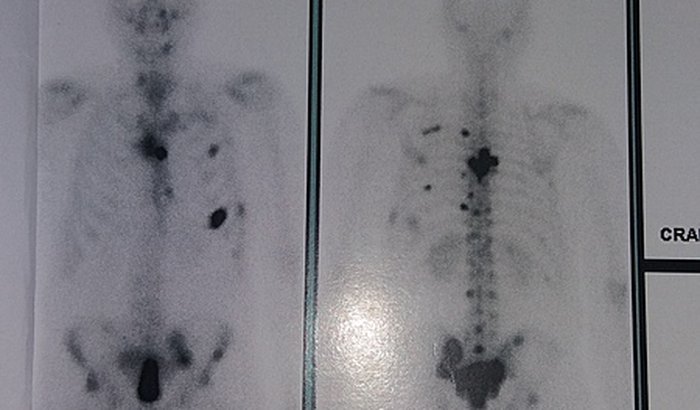

Queridos amigos, amigas, conhecidos e pessoas solidárias ,fui diagnisticado com câncer na próstata e com metástase nos ossos como podem ver na foto acima . Me ajudem gente eu preciso e o tempo está passando e quero muito viver, ficar CURADO. O bondoso INSS indeferiu meu pedido(negou) meu pedido de beneficio POR INCAPACIDADE.

Sou de Barbacena MG , professor de inglês e com a pandemia fiquei sem qualquer tipo de renda. Os sintomas começaram em dezembro 2019, com excesso de idas ao banheiro, sensação de bexiga cheia e não saia nada e por fim incontinência urinária.Em janeiro de 2020, os sintomas pioraram. O médico disse que podria ser hiperplasia. Tomei antibiótico por 45 dias e nada mudou. Ele então solicitou uma biópsia. Dei entrada com o pedido da biópsia e o SUS marcou para 90 dias depois e ainda cancelaram 3 dias antes. Por tempo indeterminado. Foi quando um médico amigo pagou para que eu fizesse e por ver meu sofrimento. Chegou ao grau agressivo 4 sendo que o máximo é de 5. Fui desenganado por um médico. Mas fé é tudo, quem determina é DEUS. Gente é muita dor e apesar da minha Fé, a insegurança chegou a falar mais alto. Porém, falei que ficaria curado em nome de Jesus , das orações e da ajuda financeira, pois tudo é muito caro.E para que eu tenha um tratamento digno , PRECISO de Vocês. Primeiro coloquei nas mãos de Jesus nosso Deus e tenho Fé de que ELE que nunca nos abandona, já está fazendo a obra DELE . AGORA CONTO COM SUA DOAÇÃO PARA QUE EU POSSA TER A SUA SOLIDARIEDADE NAS CONTRIBUIÇÕES . EU VOS PEÇO COM MUITA FÉ, AMOR E JÁ DEIXO MINHA GRATIDÃO.